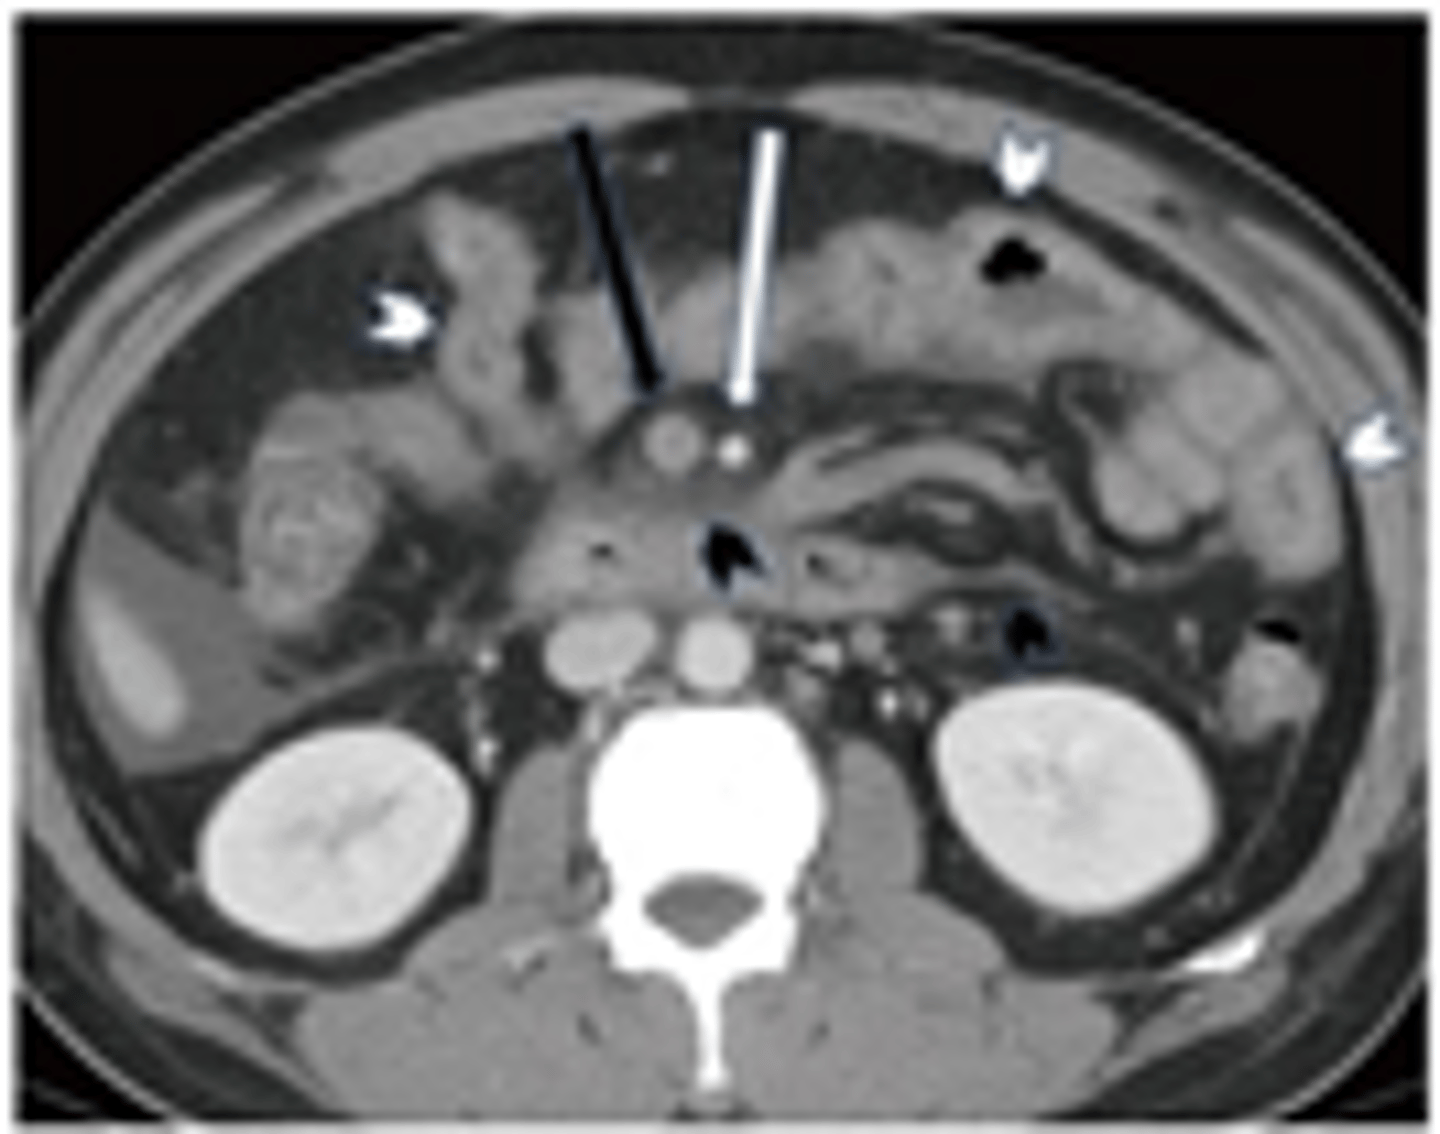

Imaging of choice for suspected dx?

CT without oral contrast (95% sensitive; dx = Acute Mesenteric Ischemia) or CTA if CT is inconclusive (100% PPV, but not great for pts with AKI)